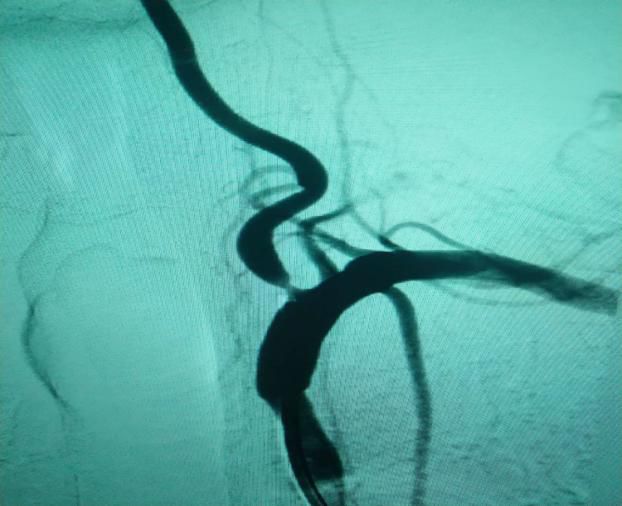

(6)2018年12月13日开展第一例颅内动脉瘤栓塞术。

患者:赵某  女性 48岁 河南省光山县

图片